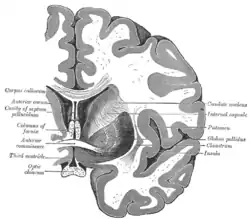

Coronal cross-section of brain showing the corpus callosum at top and the anterior commissure below | |

The commissural fibers make up tracts that include the corpus callosum, the anterior commissure, and the posterior commissure.

Corpus callosum

Anterior commissure

The anterior commissure (also known as the precommissure) is a tract that connects the two temporal lobes of the cerebral hemispheres across the midline, and placed in front of the columns of the fornix. The great majority of fibers connecting the two hemispheres travel through the corpus callosum, which is over 10 times larger than the anterior commissure, and other routes of communication pass through the hippocampal commissure or, indirectly, via subcortical connections. Nevertheless, the anterior commissure is a significant pathway that can be clearly distinguished in the brains of all mammals.